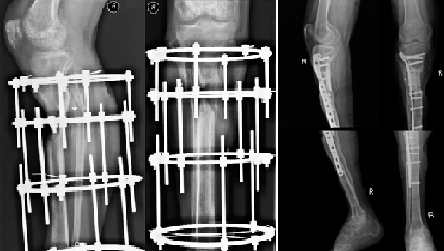

Мужчина обратился за помощью по поводу дефекта правой большеберцовой кости и укорочения правой голени до 17 см. Дефект большеберцовой кости образовался в результате ранения. Пациенту, в связи с невозможностью восстановить длину конечности было предложено выполнить ампутацию на уровне бедра.

Нами было проведено реконструктивно-восстановительное лечение, в котором были использованы клеточные технологии и метод Елизарова. В результате проводимого лечения дефект большеберцовой кости был замещен и восстановлена длинна конечности.

Через полтора года пациент смог пользоваться своей правой ногой.